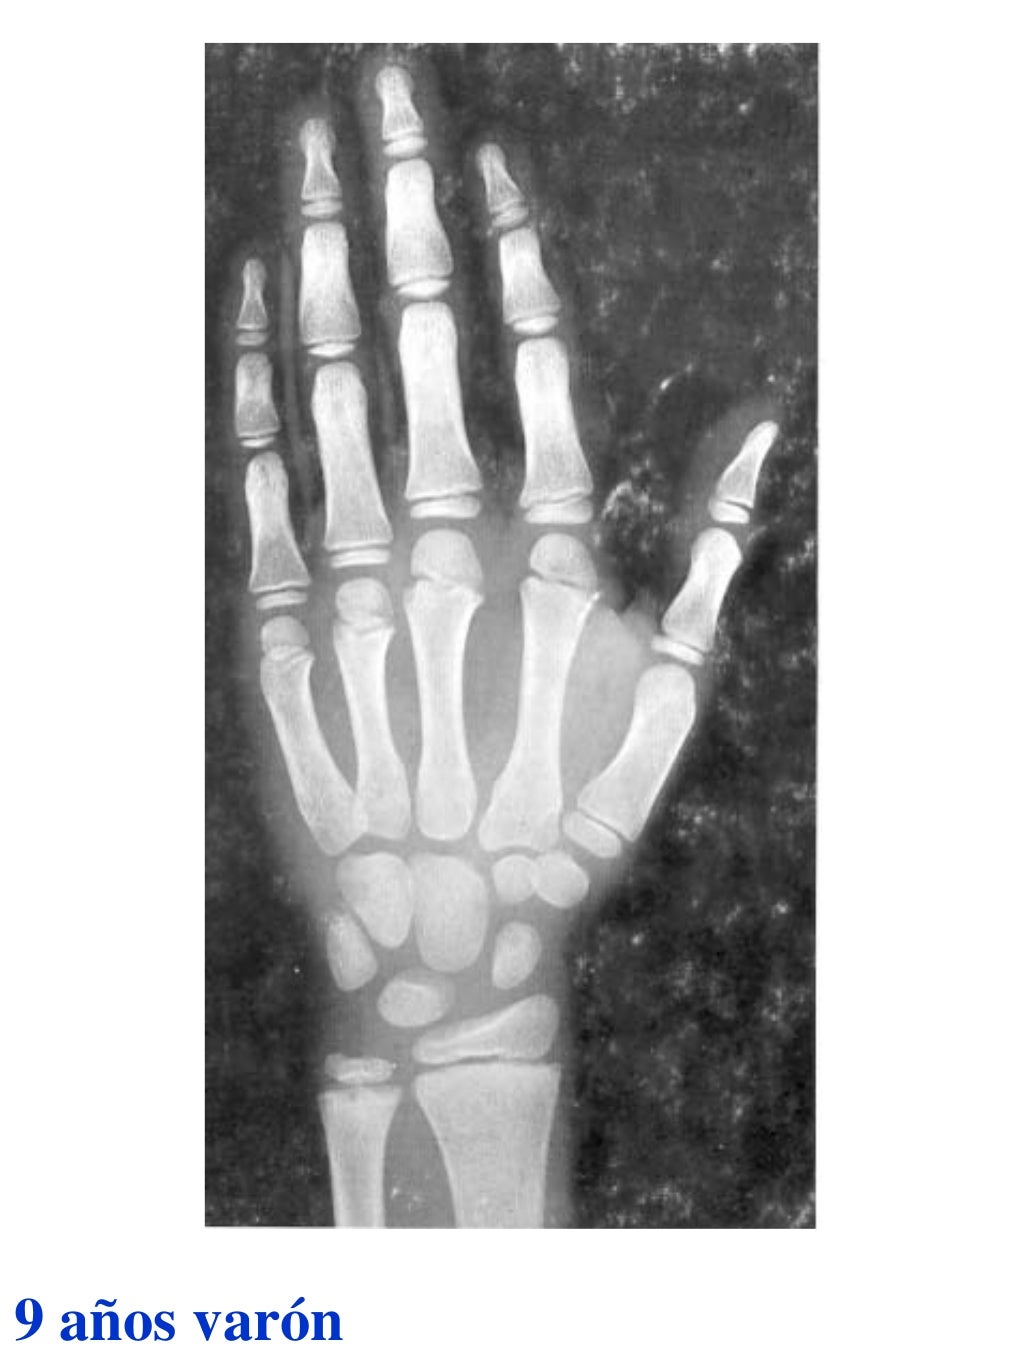

Tablas De Greulich Y Pyle . Scribd is the world's largest social reading and publishing site. This systematic review summarizes the. The radiographic atlas of skeletal development of the hand and wrist by ww greulich and si pyle is a classic radiological. The standards established by greulich and pyle, undoubtedly the most popular method, consist of two series of standard plates. The greulich and pyle method is one of the two main ways to assess the bone age of children. El documento lista las edades. Both main methods of bone age. 153 recomendaciones • 616,869 vistas. Atlas greulich y pyle | pdf | descarga gratuita. The greulich and pyle atlas is used to estimate the age of children and adolescents.

Tablas De Greulich Y Pyle The standards established by greulich and pyle, undoubtedly the most popular method, consist of two series of standard plates. The standards established by greulich and pyle, undoubtedly the most popular method, consist of two series of standard plates. El documento lista las edades. This systematic review summarizes the. The greulich and pyle method is one of the two main ways to assess the bone age of children. Both main methods of bone age. Scribd is the world's largest social reading and publishing site. 153 recomendaciones • 616,869 vistas. Atlas greulich y pyle | pdf | descarga gratuita. The greulich and pyle atlas is used to estimate the age of children and adolescents. The radiographic atlas of skeletal development of the hand and wrist by ww greulich and si pyle is a classic radiological.